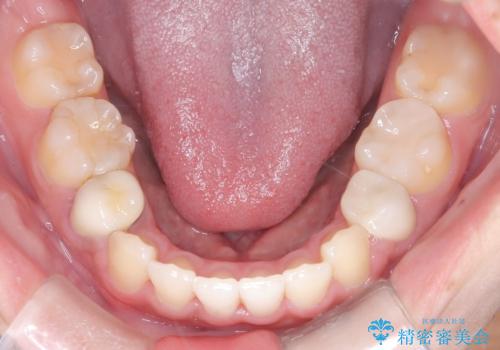

抜歯によって前歯を下げるためのスペースを確保。その後、審美ワイヤー矯正を用いて、歯列全体のバランスを整えながら前歯を後方へ移動させました。治療後は、横顔のラインが整い、自然な口元になったことで、見た目も噛み合わせも改善しました。患者様からは「口元がすっきりして、自信を持って笑えるようになった」と喜びの声をいただきました。